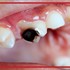

کرم‌خوردگی دندان از کجا شروع می‌شود: راهنمای مرحله به مرحله

کرم‌خوردگی دندان فرآیندی تدریجی است که معمولاً بدون درد و علامت مشخص شروع می‌شود. شناخت مرحله آغازین پوسیدگی می‌تواند به ...

روش های درمان پوسيدگی دندان و مراحل پوسیدگی دندان ها

درمان پوسيدگی دندان پوسیدگی دندان آسیبی است که به دندان‌های شما وارد می‌شود و می‌تواند منجر به ایجاد حفره، آبسه دندان یا ...